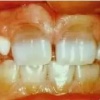

Sügav hambumus või sügav kattumine eesmiste hammaste osas

Normaalse hambumuse puhul katavad ülemised eeshambad alumisi 1/3 krooni pikkuse ulatuses ning alumiste eeshammaste lõikeserv on kontaktis ülemiste lõikehammaste suulaepoolse pinnaga. Sügavhambumuse puhul katavad aga ülemised hambad alumisi lõikehambaid rohkem...